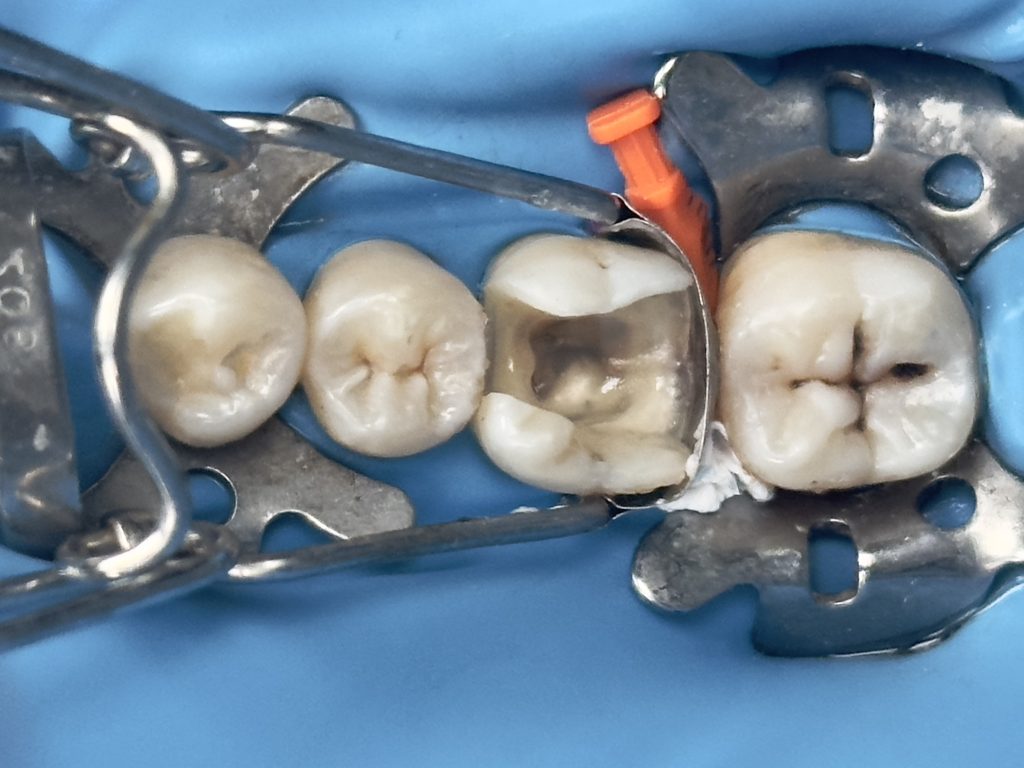

( tip : transfer the rubber dam strap between tooth no.6 &7 with blunt instrument to the contact between tooth no.5&6 rather than removing the entire RD sheet to trim the gingiva

then put it back to its position after the trimming) this controls the bleeding & saves time

-IDS & RC

-DME (matrix sealed with teflon &diamond wedge)

-ever X posterior to increase fracture resistance

2nd visit :-

-preparation & impression